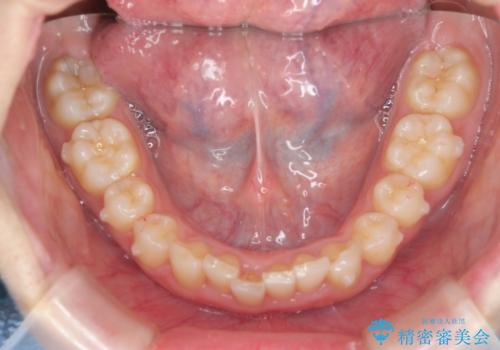

前歯のがたつき 深い噛み合わせを改善したい

- 「前歯のガタつきをきれいにしたい、噛んだ時に下の前歯が見えないことを改善したい」とマウスピース矯正を希望され来院されました。

マウスピースに加え、矯正用マイクロインプラントやゴムを併用し、がたつきや噛み合わせの深さを改善していきます。

ゴムかけやマウスピースの装用時間、しっかりとマウスピースをはめ込むチューウィーをしっかりと使用したことで良好な治療結果を得ることができました。